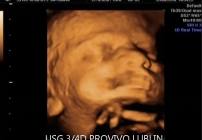

BADANIE USG 3/4D umożliwa dokładny wgląd w rozwój płodu, pozwala na podglądnięcie dziecka w sposób niemalże identyczny z jego aktualnym wyglądem.

W trakcie trwania badania obraz rejestrowany jest na płycie DVD, tak aby każdy przyszły rodzic mógł ponownie odtworzyć badanie w domowym zaciszu. Podczas badania płodu USG 3/4D istnieje również możliwość wydruku zdjęć w formacie kartki pocztowej(148 × 100 mm). Doskonałą jakość, którą charakteryzują się wykonywane przez nas odbitki cyfrowe uzyskujemy dzięki używaniu wyłącznie markowych papierów fotograficznych.